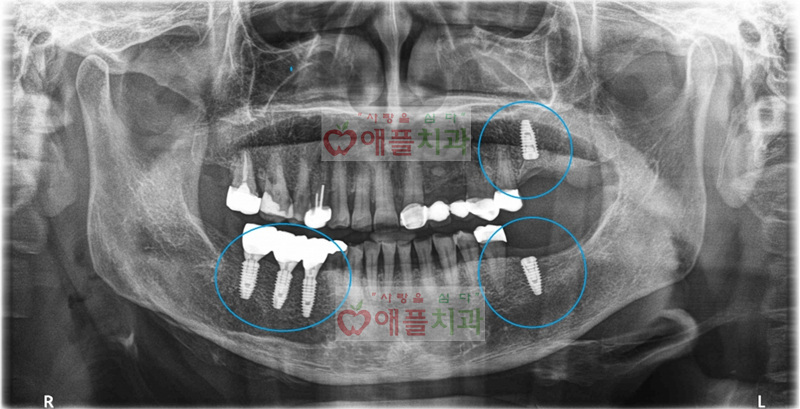

<처음 내원시 >

아래의 엑스레이에서 빨간원 부위의 치아가 많이 흔들리고 아파서하셨습니다. 발치후 임플란트 설명드렸습니다.

파란원 부위는 오래전에 이미 발치하셨다고 합니다.